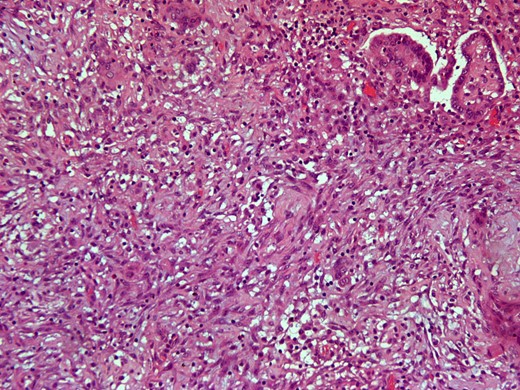

Here we report on a 32-year-old patient who presented at the Emergency Department complaining of acute abdominal pain accompanied by vomiting and diarrhea that had started three hours before. The patient was a para 2 and the latter delivery had occurred nine months before. She had been breastfeeding until 20 days before her ED visit and her menses had not yet resumed. Her medical history was unsignificant and she reported a laparoscopic ovarian cystectomy five years before, of which the histology report was not retrieved. She also had an ultrasound six months before, which described a pelvic multilocular cystic lesion of 11.4 × 8,6 × 12.3 centimeters, which remained untreated. The patient underwent an IV contrast—enhanced abdominal CT which demonstrated sizeable multilocular bilateral ovarian cystic lesions, of 18 cm and 15 cm in dimensions (in the right and left ovary respectively). (Figs 1 and 2). Her tumor markers were as follows (normal values are in parentheses): CA 15.3 = 20.53 U/ml (<25 U/ml), AFP = 1.08 ng/ml (<7 ng/ml), CEA = 0.63 ng/ml (<3.8 ng/ml), CA 125 = 110.40 U/ml (<35 U/ml), CA 19.9 = 50.06 (<34 U/ml), CA 72.4 = 6.74 (<6.9 U/ml). After the completion of preoperative investigations, the patient underwent and exploratory laparotomy. Frozen section revealed bilateral serous borderline tumors, therefore the patient underwent a total abdominal hysterectomy/bilateral salpingoophorectomy and epiplectomy. During surgical procedure astonishing remarks was the necrotized torsion of ovarian masses mimicking infiltrated ovarian neoplasm. (Figs 3–5). The final histology report confirmed the diagnosis of bilateral serous borderline tumors/atypical serous proliferative tumors, staged as pT1cNxMx or FIGO Ic. (Figs 6 and 7). Peritoneal fluid cytology showed mesothelial reactive lesions. The patient’s postoperative course was uneventful. The Multidisciplinary Team Meeting decided on adjuvant chemotherapy (four cycles of CarboTaxol; paclitaxel and carboplatin). Nine months after surgery, the patient remains alive and disease – free.

Intersection of demoplastic non-invasive autoimplantation / auto implant. (H&E × 200).